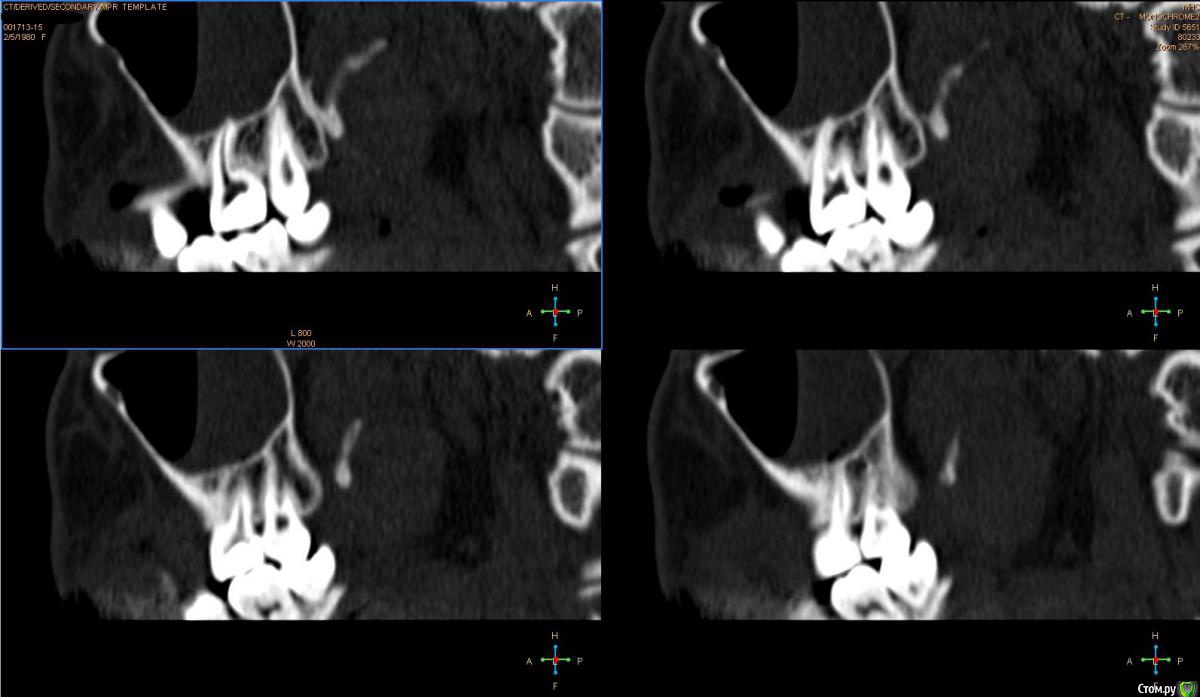

Лисица Опубликовано 26 июля, 2015 Автор Поделиться Опубликовано 26 июля, 2015 (изменено) Вы же не думаете, что Вам назначат а/б терапию по интернету? Я просто не знаю, исходя из каких показателей она назначается. Поэтому осведомилась на всякий случай. Итак, сходила я сегодня на КТ. И по ходу мне сделали что-то не то... Когда я обратилась в клинику, я уточнила, что мне нужно КТ для эндодонтии, чтобы видно было каналы, с достаточным разрешением, чтобы было видно зубы и их корни, входящие в верхнечелюстной синус. Администратор клиники уточнила у врача и сказала, что мне нужно заказывать не КТ верхней челюсти, а КТ пазух. У рентгенолога я также повторила все описанное, рассказала, что при лечении каналов вчера была продырявлена пазуха, уточнила, будут ли видны как следует зубы и их каналы, меня заверили, что "все будет". Причем у врача, судя по описанию на сайте клиники, была ординатура по хирургии в медико-стоматологическом университете, так что он, уж наверное, понимал, что мне нужно. В итоге я получила пленку со снимками формата чуть ли не А3 и диск. На пленке все зубы были просто белыми и коронки видны не целиком. Заключение: в правой верхнечелюстной пазухе уровень жидкости, острый правосторонний гайморит.Думала, может в программе можно будет увеличить разрешение. Но похоже, что нет... или я просто ламер? Зубы просто размытые и белые... Прилагаю сделанные мной скриншоты, как мне кажется, наиболее показательные... Если нужно другие "виды", то скажите какие, или такие снимки вообще ни о чем? Программа просмотра называется Philips DICOM Viewer R3.0-SP03. Аппарат был не местный "на голову", а здоровый, куда заезжаешь в лежачем положении. Изменено 26 июля, 2015 пользователем Лисица Ссылка на комментарий

Лисица Опубликовано 26 июля, 2015 Автор Поделиться Опубликовано 26 июля, 2015 Тьфу ты, Акелла промахнулся. Не та сторона в профиль. Вот парочка проекций с нужной больной стороны. Ссылка на комментарий

St. Опубликовано 27 июля, 2015 Поделиться Опубликовано 27 июля, 2015 Гайморит справа есть, и жидкость тоже. Корни этого зуба действительно заканчиваются в гайморовой.Ничего такого страшного, чтоб однозначно удалять зуб я не вижу. С гайморитом - к лорам на лечение.В зубе я бы ещё раз поменяла лекарство на пару недель, пока гайморит не притихнет, потом постоянно пломбировать. 1 Ссылка на комментарий

Лисица Опубликовано 27 июля, 2015 Автор Поделиться Опубликовано 27 июля, 2015 St., большое спасибо за ответ! Моя врач планировала закрыть его в среду (зная о том, что пазуха проткнута). Если запломбировать, пока воспаление есть, какие могут быть проблемы? И еще она сказала, что нащупала 4-й тонкий канал, но не было времени его прочистить, так что она оставила как есть до среды. Сказала, что почистит и сразу же закроет. Судя по КТ, корня 3, значит в одном из них 2 канала? В 3D похоже, что корни с медиальной стороны сросшиеся какие-то... и на небном тоже борозда. Ссылка на комментарий